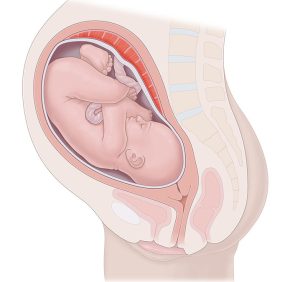

Mu buryo busanzwe, umwana aba yicaye mu nda ku buryo umutwe ari wo uri hasi mu nkondo y’umura, kugira ngo kubyara bigende neza. Iyo bigenze ukundi, biba ari malpresentation.

Mu buryo busanzwe, umwana aba yicaye mu nda ku murongo uhuza umutwe n’ikibuno, kandi umutwe ari wo uri hasi mu nkondo y’umura kugira ngo kubyara bigende neza.